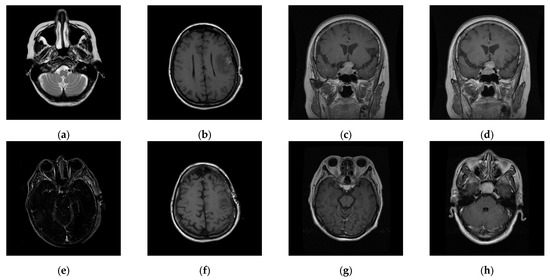

The experiments were conducted on two systems. The first system ran on Ubuntu 22.04, equipped with an Intel i7-9700KF CPU @ 3.60GHz (8 cores), an Nvidia GeForce RTX 3090 GPU, 32 GB of RAM, and Pytorch (https://pytorch.org/) for the experimentation. The second system, called the Type 1 device, is a notebook with an Intel(R) Core (TM) i7-10510U CPU @1.80 GHz 2.30 GHz, 16.0 GB RAM, 64-bit Windows operation system, and GPU MX 250. The third system, called the Type 2 device, is a notebook with an 11th Gen Intel(R) Core(TM) i5-11400H @ 2.70 GHz 2.69 GHz, 24.0 GB RAM, 64-bit Windows operation system, and GPU Nvidia GeForce 3060. The second system is a notebook that was released around 2019 or early 2020. The third system is also a notebook that was released in early 2021. The two systems were used to simulate resource-constrained environments. Different medical and test images were used as the test images to evaluate the performance of our proposed scheme and to make comparisons between our scheme and Qin et al.’s scheme [20]. In the first experiment, eight medical images, which are MRI scans of the brain, were randomly selected from the Osirix database [21] as test images and are presented in Figure 10 to demonstrate the performance of our proposed scheme in detail. In the second experiment, one hundred medical images, which are also MRI scans of the brain, were randomly selected from the Osirix database [21] to form Dataset 1 and Dataset 2, as shown in Figure 11, to prove the stable performance of our proposed scheme. In the third experiment, six general grayscale images, sized 512 × 512, demonstrated in Figure 12, were used to compare with those offered by Qin et al.’s scheme [20]. The logo depicted in Figure 13a was used as the watermark for the first and the second experiments and Figure 13b was used as the watermark for the third experiment.

4.2. Performance Analysis

To prove the performance reported in Section 4.1 is stable even when the number of test images is increased and the types of medical images vary, in the second experiment, one hundred medical images randomly selected from the Osirix database [21] to form Dataset 1 and Dataset 2, as shown in Figure 11, and were used to evaluate the stability of our performance. Experimental results are listed in Table 5. It is worth noting that the LSB data hiding strategy is listed alongside our designed DWT-based data hiding strategy in Table 5 to demonstrate that our proposed VUF-MIWS framework can seamlessly integrate with different data hiding strategies.

Figure 11. Two datasets are used to test the stable performance of the proposed scheme. (ad) are Dataset 1, images of the pituitary gland taken from back to front. (eh) are Dataset 2, images of the pituitary gland taken from top to bottom.